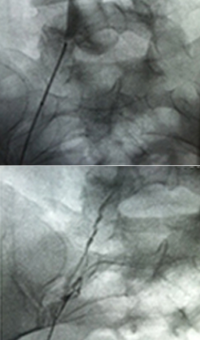

Acute DVT left lower extremity revascularization

47 year old male presented with leg swelling ~2 weeks.

Procedural steps

• Power Pulse delivery of 10mg tPA followed by

• 20 minute dwell time

• Total runtime was 300 seconds

Acute DVT Left Lower Extremity Revascularization pre-treatment angio.

Acute Iliofemoral thrombus pre-treatment

IVC Filter placed (left image)

Acute DVT Left Lower Extremity Revascularization post-treatment.

Post ZelanteDVT  pharmacomechanical thrombectomy

Case images courtesy of David Wilson M.D. – Harbin Clinic, Rome, Georgia – December 19, 2015